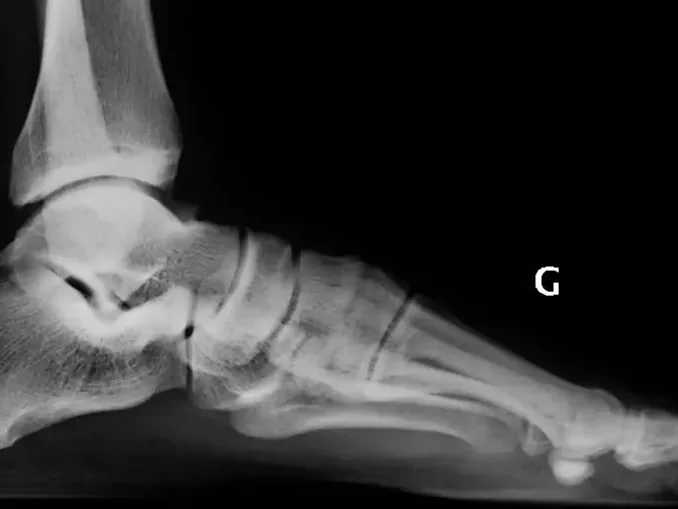

Le symptôme douloureux est le principal motif de consultation pour nos patients. Le pied est une zone anatomique soumise à des fortes contraintes, susceptible d’être le siège de nombreuses douleurs.